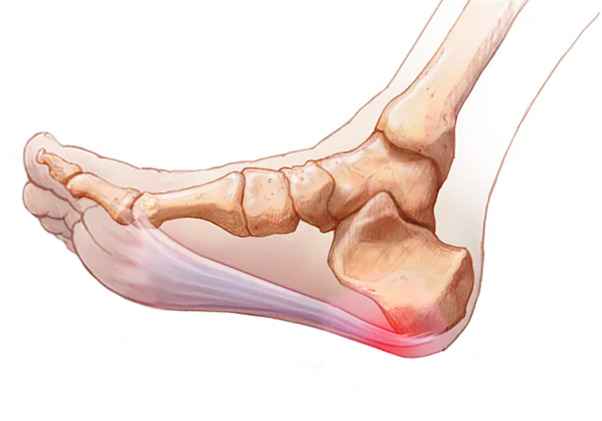

也叫跖腱膜,起自跟骨结节的前内侧面,向远端扩展至5个足趾下形成束带,是一种厚韧的纤维腱膜。它的功能主要是维持足弓和保护足底组织。

人在步行时会反复牵拉跖腱膜,从而重复牵拉跟骨结节。当肥胖或足部力量减弱时,跖腱膜牵拉跟骨结节的力量增大,会使跖腱膜发生退变,引起疼痛。

跖腱膜的解剖结构

跖腱膜发生退变的部位